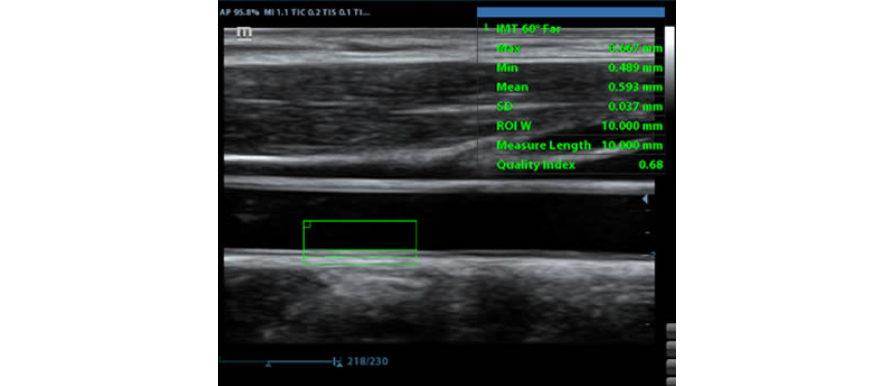

IMT (Intima-Media Kal?nl?k)

GÞvenilir karotid durum bilgisi sa?layan anterior ve posterior duvar kal?nl???n?n otomatik ?l?ÞmÞ.